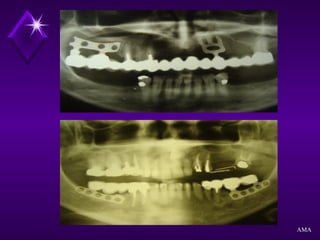

EXAME RADIOGRÁFICO

Radiografias Periapicais

Radiografia Panorâmica

Radiografia de Perfil

Planigrafias

Tomografia Computadorizada

AMA